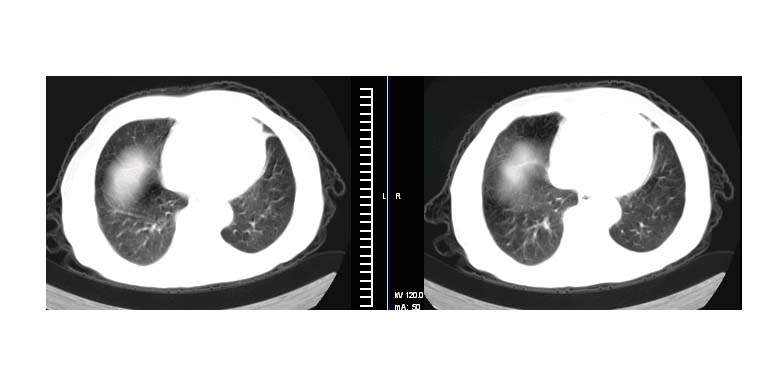

标题: CT11087:男性,82.咳嗽一周.抗炎治疗4-5天效果不明 [打印本页]

标题: CT11087:男性,82.咳嗽一周.抗炎治疗4-5天效果不明

考虑左上肺癌,似与左侧肋骨关系密切?

左上肺周围型肺癌伴纵隔淋巴结转移

左肺上叶尖段周围型肺癌伴左肺门淋巴结转移。

左上肺实质性肿块,浅分叶 毛糙 胸膜凹陷征 纵隔淋巴结肿大——支持:左肺上叶周围型肺癌!

左上肺软组织肿块,有分叶,短毛刺,气管旁间隙见有肿大淋巴结,考虑左上周围型肺癌伴纵隔淋巴结转移。